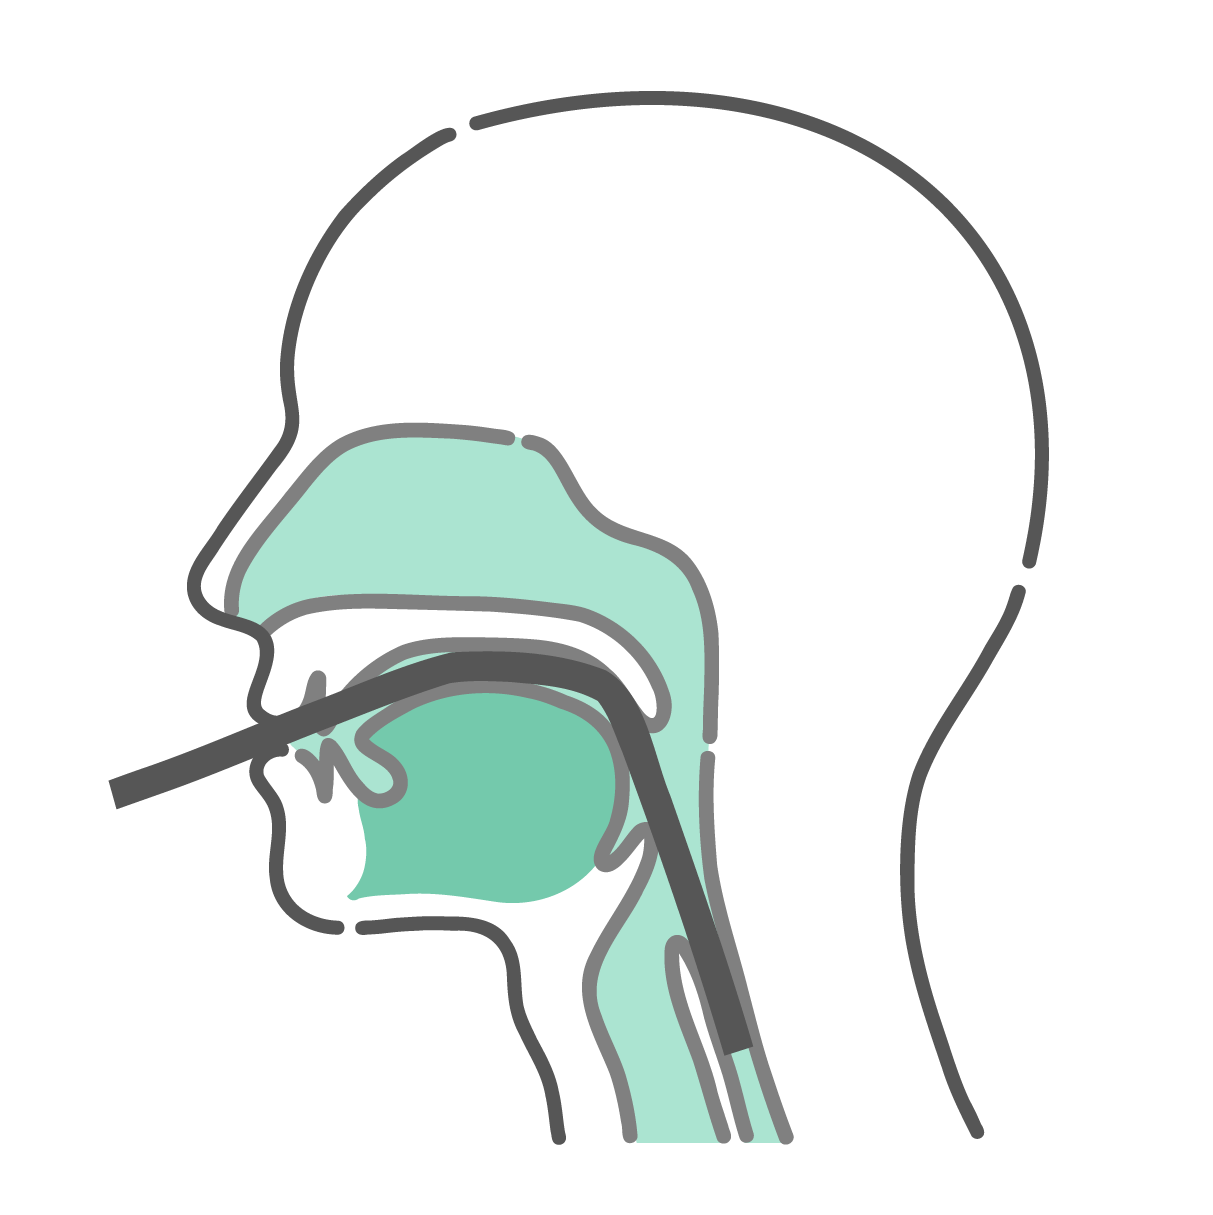

口からスコープを挿入する「経口内視鏡検査」のメカニズムを解説した解剖断面図です。スコープが舌の根元(舌根)に触れながら通過する様子を描いています。この舌根への接触が強い嘔吐反射(オエッとなる反応)を引き起こす原因であることを、医学的に説明する資料やWebサイトに最適です。

健康器具・機器口からスコープを挿入する「経口内視鏡検査」のメカニズムを解説した解剖断面図です。スコープが舌の根元(舌根)に触れながら通過する様子を描いています。この舌根への接触が強い嘔吐反射(オエッとなる反応)を引き起こす原因であることを、医学的に説明する資料やWebサイトに最適です。